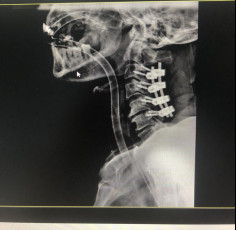

(術(shù)后拍片)

今年5月,張阿伯出院近2月后,大部分生活已經(jīng)可以自理。戈主任為張阿伯做了復(fù)查診治,結(jié)果顯示他的頸椎固定可靠,復(fù)位良好,病體正在朝理想的康復(fù)方向發(fā)展。